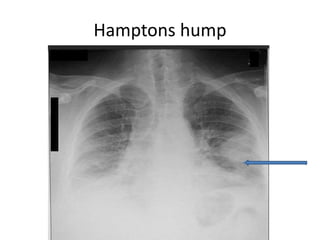

Chest x ray

A normal or nearly normal chest x-ray often

 Others -

1. focal oligemia (Westermark's sign),

2. a peripheral wedged-shaped density above the diaphragm

(Hampton's hump)

3. an enlarged right descending pulmonary artery (Palla's sign

4. Pleuropulmonary opacities

5. Pleural effusion

6. Linear shadows

7. prominent RV

Hamptons hump